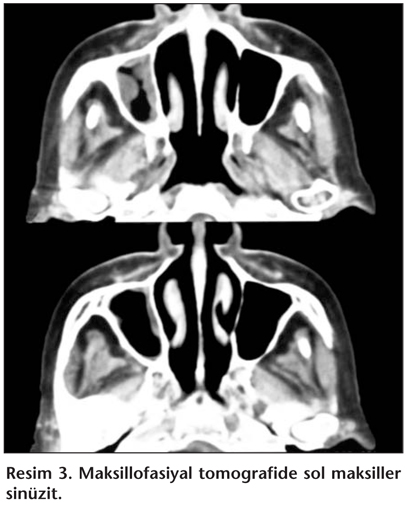

Kliniğe yatırıldıktan sonra hastadan asido rezistan basil (ARB) incelemesi için ardışık üç kez balgam ve idrar, bakteriyel, mikobakteriyel ve fungal kültür örneği alındı. Pürifiye protein derivesi negatif ölçüldü. ARB görülmeyen ve kültürlerinde bakteri ve fungus üremesi olmayan hastanın örnekleri tüberküloz için inkübasyonda tutuldu. Yüksek ateş, trombositoz ve CRP yüksekliği olan hastaya tüm kültürleri alındıktan sonra klinik ve patolojik destekleyiciler nedeniyle piridoksin ile birlikte ampirik dörtlü (izoniazid 1 x 300 mg, rifampisin 1 x 600 mg, pirazinamid 25 mg/kg, etambutol 15 mg/kg) antitüberküloz tedavi başlandı. Hastanın kliniğe yatışından sonra ara ara az miktarda burun kanaması oldu ve bunun dış merkezde yapılan nazal girişimli bronkoskopi sonrası mukozal tahrişe bağlı olabileceği düşünüldü. Yatışının ikinci haftasında sol ayakta hipoestezi ve parezi gelişti. Nöroloji anabilim dalı ile konsülte edilen hastada nöropati düşünüldü ve EMG ile doğrulandı. Ancak yaygın akciğer parankim tutulumu olan ve tedavinin 15. gününe rağmen klinik ve laboratuvar bulgularında düzelme saptanmayan hastanın dış merkezde değerlendirilmiş akciğer parankim biyopsilerinin yeniden hastanemizde incelenmesi planlandı. Değerlendirilmeye alınan bu örnekler "nekrotizan granülomatöz inflamasyon" olarak raporlandı. Dokuda yapılan tüberküloz polimeraz zincir reaksiyonu negatif saptandı. Bunun üzerine nekrotizan granülomatöz tabloların ayırıcı tanısına gidildi. Hastanın burun akıntısı öyküsü ve son dönemde olan burun kanamaları düşünüldüğünde hastaya maksillofasiyal tomografi ve PR3-ANCA istendi. Tomografide maksiller sinüzit saptandı (Resim 3). PR3-ANCA pozitif idi. İdrarda mikroskobik hematürisi vardı. WG kriterlerinin hepsini karşılayan hastanın tüberküloz tedavisi kesildi. Siklofosfamid intravenöz yüksek doz infüzyon (tek doz) ve prednizolon 2 mg/kg tedavisi başlandı. Tedavi öncesi nazal sürüntü kültürleri alınarak Staphylococcus aureus nazal taşıyıcılığı araştırıldı ancak belirlenmedi. Hastaya trimetoprim-sülfametoksazol günde tek doz fort tablet başlandı. İlk siklofosfamid dozundan iki hafta sonra ilaç tekrarlandı. Takiplerinde hastanın ateşi düştü, klinik olarak iyileşti ve akciğer bulgularında gerileme saptandı. Balgam ve idrarda Mycobacterium tuberculosis üremesi olmayan hasta prednizolon ve siklofosfamid oral tedavisi ile ayaktan izlenmek üzere taburcu edildi.